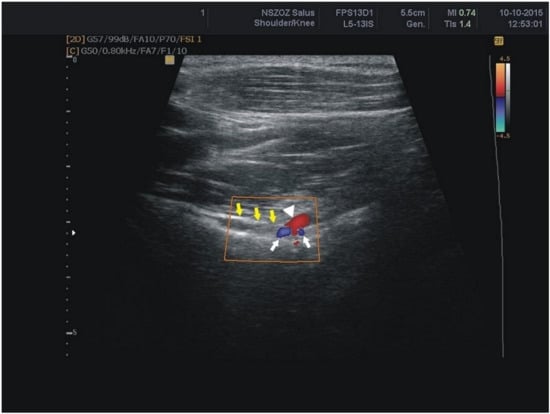

- the thickness of the soft tissue over the suprascapular artery: the minimal distance between the suprascapular artery and the skin (Figure 4A)

- the thickness of the soft tissue over the suprascapular vein: the minimal distance between the suprascapular vein and the skin (Figure 4B)

- the thickness of the soft tissue over the suprascapular nerve: the minimal distance between the suprascapular nerve and the skin (Figure 4C).